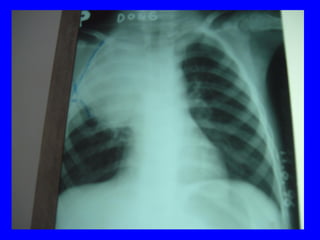

X quang phoåi:  xaùc ñònh , xñònh NN, ñoä naëng

VP thuyø, thaâm nhieãm phoåi, VP moâ keõâ

4.3 Chaån ñoaùn xaùc ñònh:

Laâm saøng: soát+ ho+ thôû nhanh vaø hoaëc co

loõm ngöïc

+ X quang: coù toån thöông phoåi: toån thöông

pheá nang; moâ keõ; toån thöông thuøy phoåi